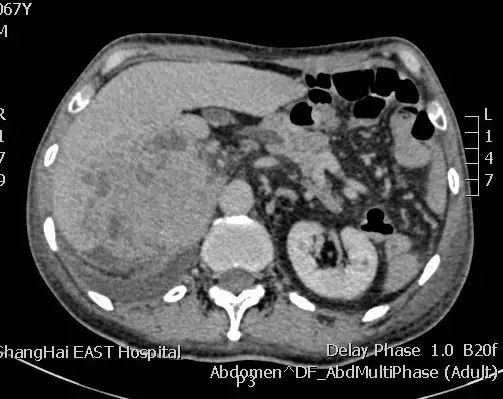

病例三:老年男性,因消化道出血入院,甲胎蛋白 >60500ng/mL,腹部CT显示右侧肾上腺区巨大占位并侵犯肝脏,肝硬化,肝右前叶有占位,胃镜显示胃窦部巨大溃疡,肺部CT显示左肺不张。